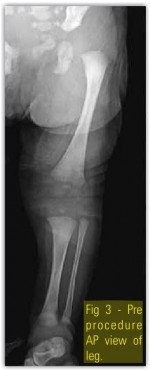

Our case was a preterm (35 weeks) baby boy born by normal vaginal delivery with history of oligohydraminios, presented with extreme hyperextension of left knee with toe almost touching the abdomen (Fig.1 ) with associated anomalies present; patient had CDH(Fig.3 and 4), Quadriceps contracture(Fig.2 ) and CTEV in the same involved lower limb. Left hip showed acetabular dysplasia. The affected left side shows presence of increase in depth of iguinal fold, abduction is limited at the left hip, the Ortolani and Barlow test was positive. Telescopic sign was positive. The feet on both side were inverted to about 30 degree and foot was pointing down wards. The ankle was in equines the feet were supinated and adducted, dorsiflexion beyond 90 degree was not possible. Tibia was normal and was not having an internal torsion. Passive stretching followed by above knee (toe to groin) POP splints was used from the first day. The basic principal of correction of adduction first followed by varus & then equines is followed. The splints were changed every seventh day with gradual bending. In about a month time knee flexion range of movement about 70 degree was achieved. There is need to be cautious at this time to avoid excessive & forceful correction as this may lead to damage to epiphysis & future growth abnormalities. As mentioned by Nogi et al, when there is concurrent presence of DDH with this knee abnormality then knee problem should be treated first as good knee movements can help with correction of hip abnormality [19]. In three months’ time, the left knee adopted a normal shape and position. The splints were discontinued and the mother was advised to continue passive stretching. The CDH was treated by abduction splints (wearing of double diapers) for six weeks. CTEV was treated with serial manipulation and POP Casts. A follow up at the age of one year showed normal position of both knees(Fig.5) as well as both hips.